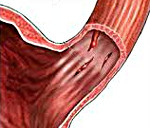

Во время сильной и многократной рвоты в брюшной полости создается избыточное давление. Стенки желудка и пищевода перерастягиваются, истончаются и разрываются в самом уязвимом месте. Обычно разрывается слизистая оболочка пищеварительного тракта, иногда — средний мышечный слой. Под воздействием провоцирующих факторов разрыв происходит быстро и полностью. При этом содержимое выходит в брюшную полость или средостение, у больных развивается перитонит или медиастенит.

При синдроме Мэллори-Вейса обнаруживают линейную трещину слизистой оболочки верхней части желудка. Обычно у больных определяется один разрыв. В крайне редких случаях их может быть 2 и более. Очаг поражения имеет длину около 3 см и расстояние между краями трещины – несколько мм. Если во время фиброгастроскопии обнаруживают кровоточащий сосуд, кровотечение сразу же останавливают.

Пусковым моментом разрыва пищеводно-желудочной слизистой обычно становится многократная рвота, резкое повышение абдоминального давления при переполненном желудке или кардиоэзофагеальном спазме, реже — прямые механические воздействия. Возникновение избыточного давления в кардиальном отделе желудка способствует перерастяжению стенки органа. При морфологической несостоятельности эпителия, вызванной воспалительными процессами, растянутая слизистая желудка, пищевода разрывается в наиболее истонченном или патологически измененном участке. Обычно разрыв распространяется не глубже эпителиального и подслизистого слоя. В тяжелых случаях повреждается мышечная, серозная желудочная либо адвентициальная пищеводная оболочки с выходом агрессивного содержимого в средостение или брюшную полость.